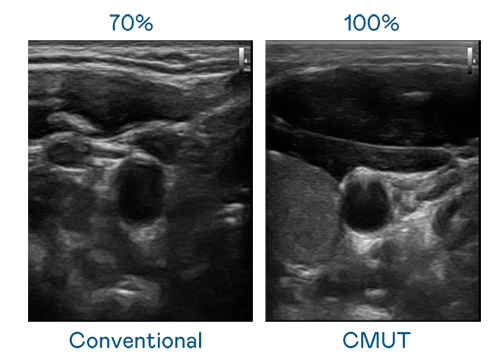

CMUT 技术是一种用电容式微机电元件来产生超音波讯号的技术。与传统 PZT 压电式技术相比,CMUT 频宽增加 30%,更宽频的超音波讯号让影像解析度大幅提升,是实现高影像品质医疗超音波扫描、促进精准医疗发展的关键技术。

大频宽带来超清晰影像

超音波影像的解析度高低,首先取决于探头能发出的讯号频宽。hhpoker俱乐部 CMUT 可提供高清晰的超音波讯号,提供高频宽、高灵敏度、影像纹理细节更高的超音波影像,协助医护人员缩短影像判读时间及利用精准的医疗影像进行诊断。